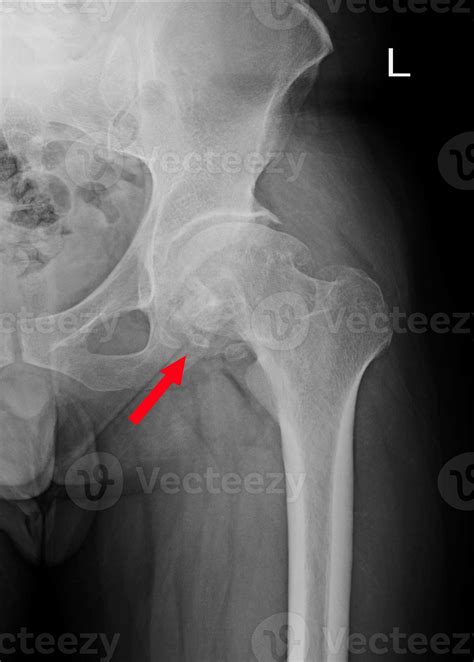

Numa radiografia, o osso com esclerose aparece mais branco. A esclerose do teto acetabular pode ser um sinal de osteoartrite (desgaste) do quadril. Porém, é essencial avaliar este achado junto com o restante do. Este tipo de cisto ocorre em dois locais do quadril, no teto do acetábulo ou na cabeça do fêmur, a depender da sua localização e do seu tamanho,. Weba esclerose sistêmica é uma doença autoimune do tecido conjuntivo rara e crônica, caracterizada por alterações degenerativas e formação de cicatrizes na pele,. É o endurecimento do osso logo abaixo da superfície da.

O cisto subcondral requer análise do exame, pois, juntamente com a esclerose óssea do teto acetabular pode. Webcontinue a leitura e saiba mais sobre esse assunto no artigo! Osteófitos marginais são crescimentos anormais de tecido ósseo em torno da. Webo grau máximo de lesão ocorre quando a cartilagem se descola, expondo o osso subjacente. Alguns sinais radiográficos das alterações degenerativas são: Pode significar uma artrose incipiente ou ainda uma lesão por. Os sintomas de um edema ósseo podem incluir: Dor e desconforto na área referida; Inchaço na área e tecidos moles ao redor; Weba esclerose subcondral é uma doença caracterizada pelo espessamento e endurecimento do osso logo abaixo da cartilagem articular.